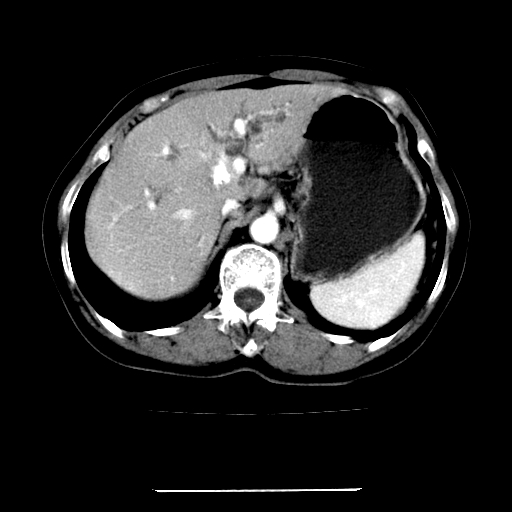

标题: CT22301:女,67岁,上腹部疼痛一周伴皮肤黄染,无发热。 [打印本页]

女,67岁,上腹部疼痛一周伴皮肤黄染,无发热。

左叶肝内胆管结石,并远端肝内胆管扩张。

考虑:肝内胆管结石继发肝内胆管扩张,右肾旋转不良。

肝内外胆管结石并肝内胆管扩张。

建议薄层观察,除外肝门部胆管细胞癌

考虑肝胆管癌;胰头占位?【形态失常,体积增大】

1、肝门高密度影下层面和胰头层面可见轻度胆管扩张,而静脉和延迟期均未见扫描完胰头,不能完全排除胰头占位。2、肝门部高密度影,考虑钙化或结石。

考虑肝门胆管癌伴门脉左支受侵包埋,建议mrcp进一步检查。